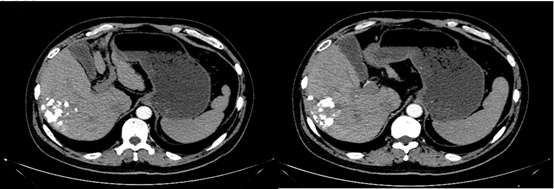

于2019年10月10日复查,检查肝增强CT示,肝脏多发占位性病变,考虑原发性肝癌,部分病变为TACE治疗后改变,其内可见肿瘤存活,对比2019年8月17日病变增多增大,碘油沉积增多。再次DSA引导下行TACE治疗。

图片

图:肝增强CT(2019-10-10)

2020年4月8日复查,异常凝血酶原7793.7 ng/ml;肝增强CT提示,肝脏多发占位性病变,考虑原发性肝癌,可见肿瘤存活,对比2019年10月10日病变增多增大。

图:肝增强CT(2020-4-8)